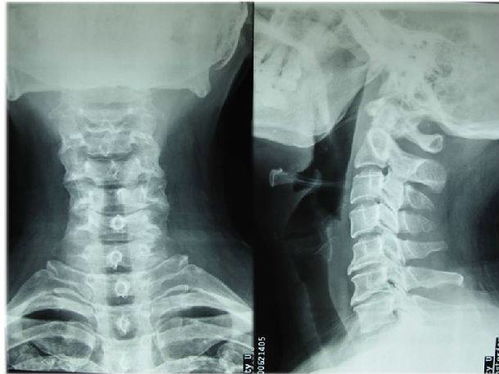

3.頸椎病人帶頸托3---6周,腰椎病人帶護(hù)腰帶3---6個(gè)月